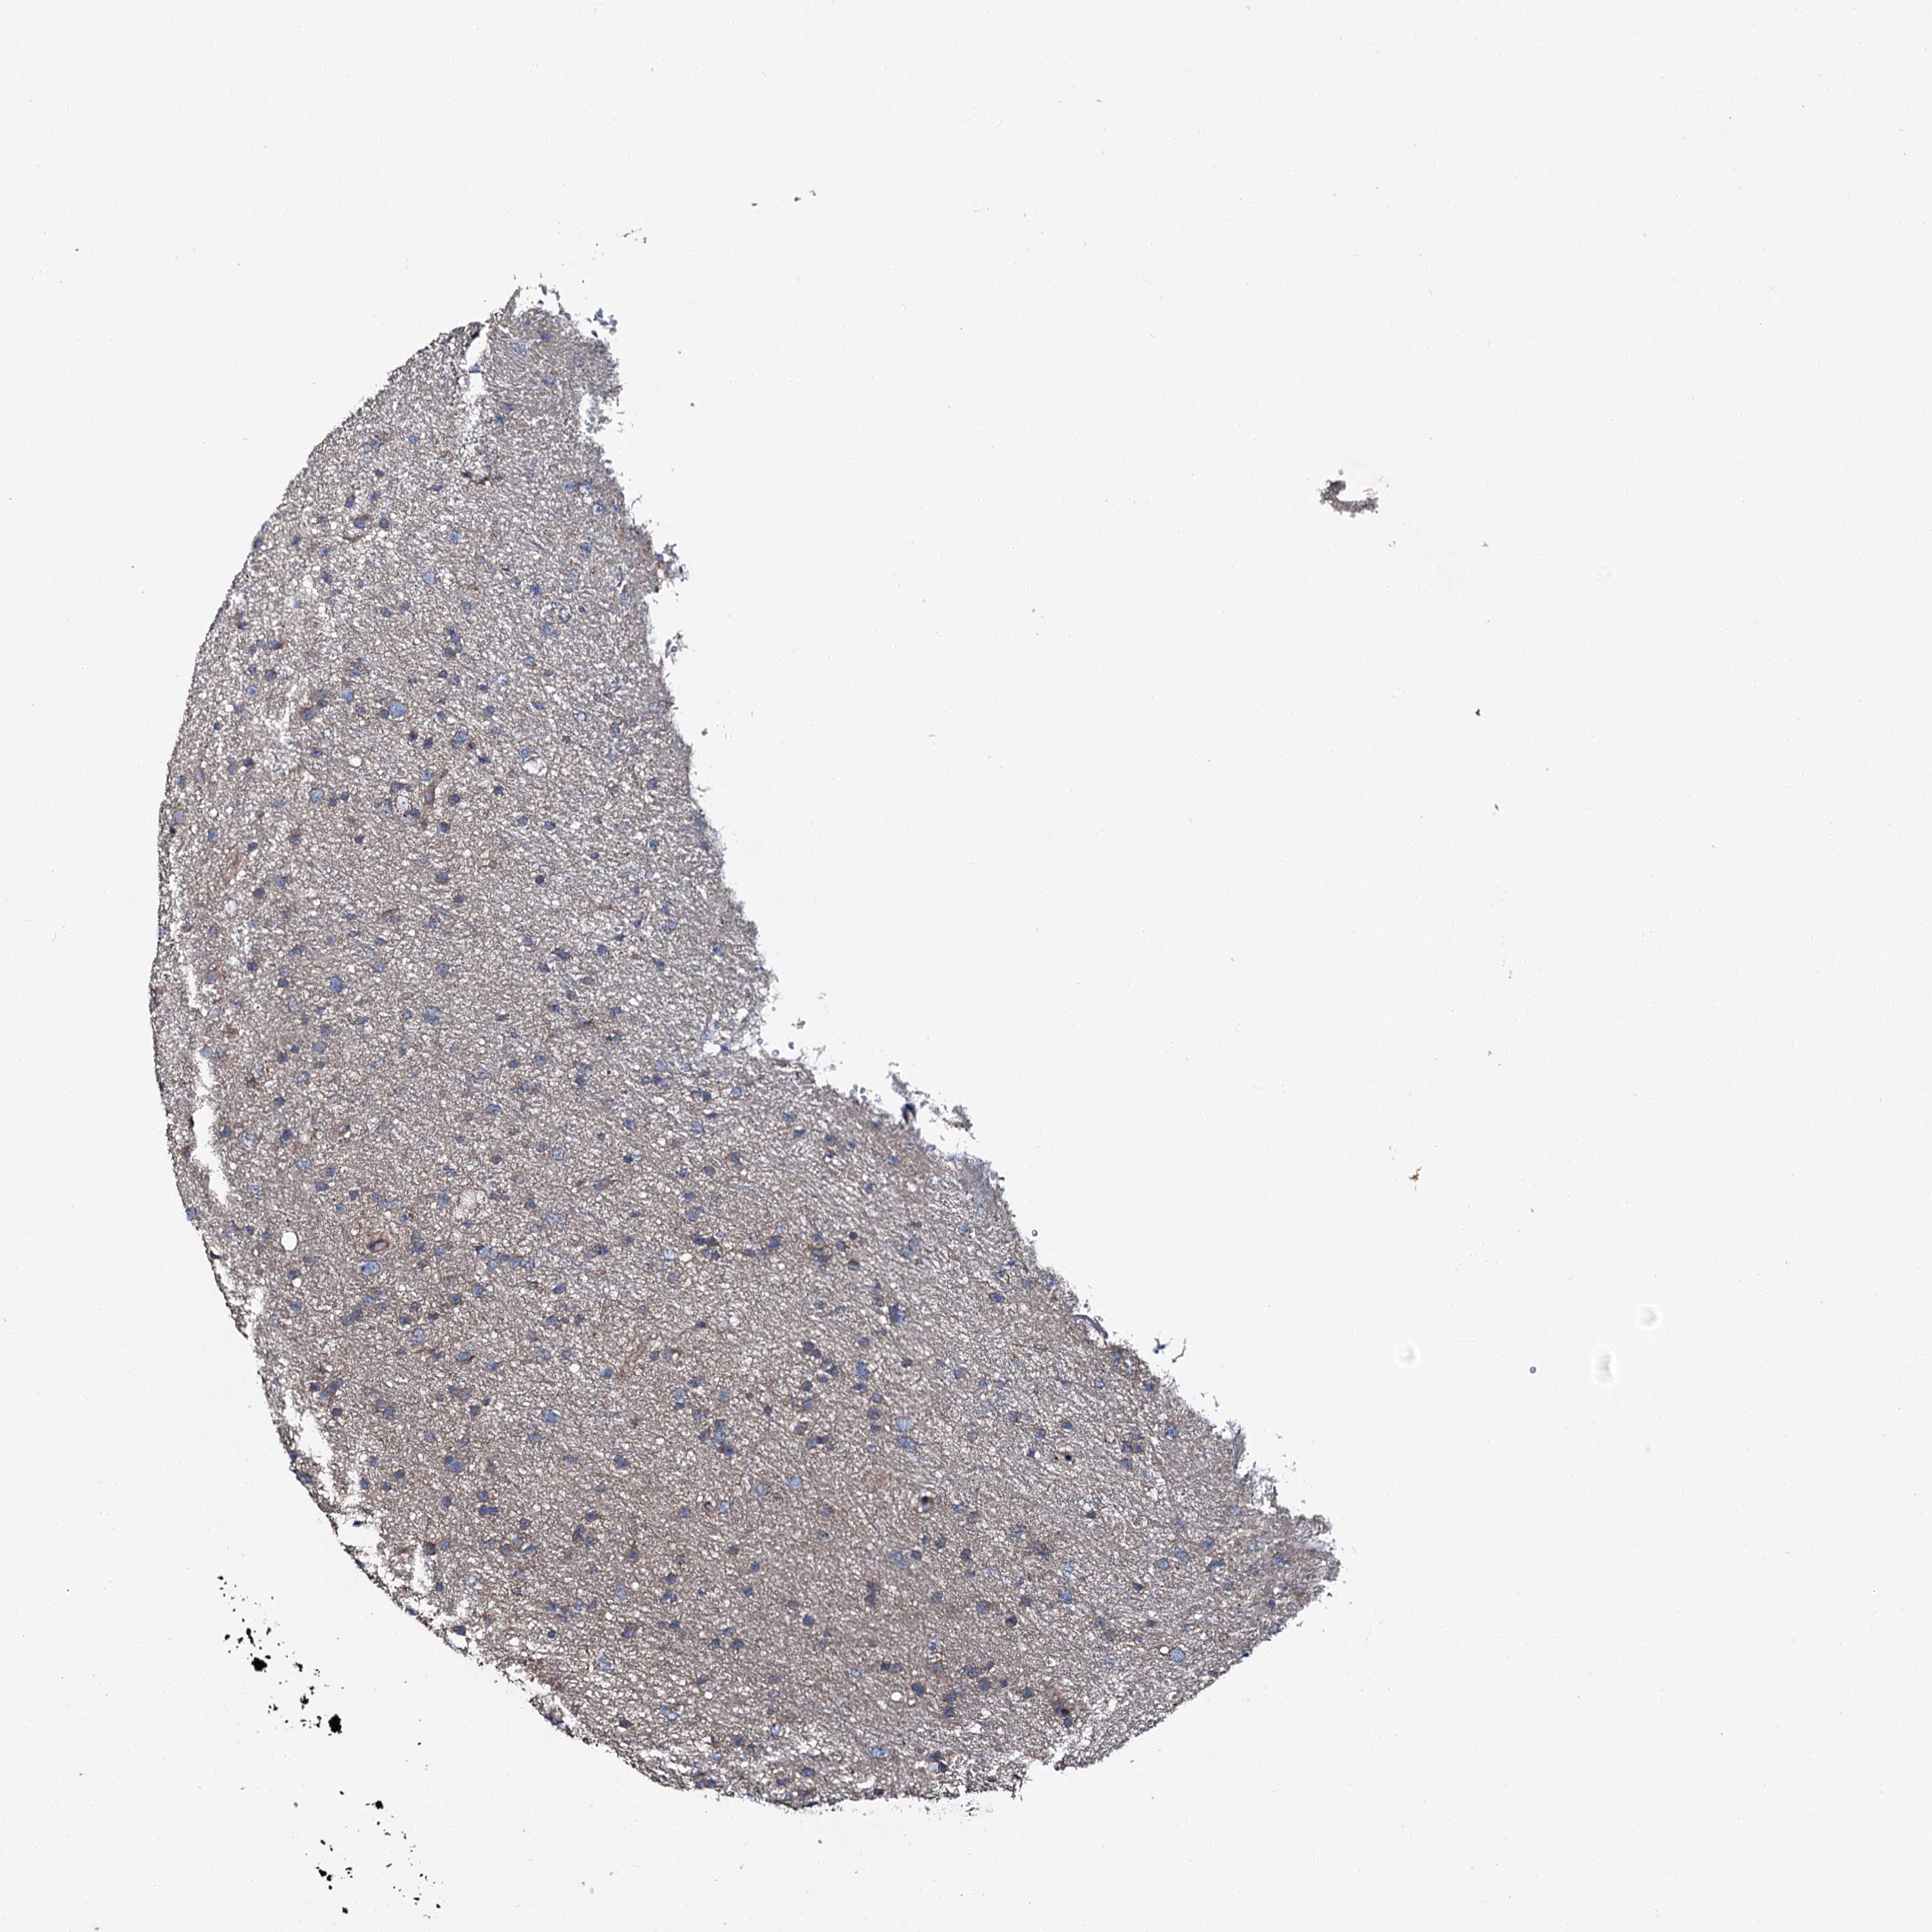

GLIOMA - Protein expressioni

A mouse-over function shows sample information and annotation data. Click on an image to view it in a full screen mode. Samples can be filtered based on level of antibody staining by selecting one or several of the following categories: high, medium, low and not detected. The assay and annotation is described here.

Antibody stainingi

Antibody staining in the annotated cell types in the current human tissue is reported as not detected, low, medium, or high, based on conventional immunohistochemistry profiling in selected tissues. This score is based on the combination of the staining intensity and fraction of stained cells.

Each image is clickable and will lead to virtual microscopy that enables deeper exploration of all samples and also displays staining intensity scores, fraction scores and subcellular localization as well as patient and tissue information for each sample.

Antibody HPA039390

Staining

High

Medium

Low

Not detected

Intensity

Strong

Moderate

Weak

Negative

Quantity

>75%

75%-25%

<25%

None

Location

Nuclear

Cytoplasmic/membranous

Cytoplasmic/membranous,nuclear

Glioma, malignant, High grade

Glioma, malignant, Low grade